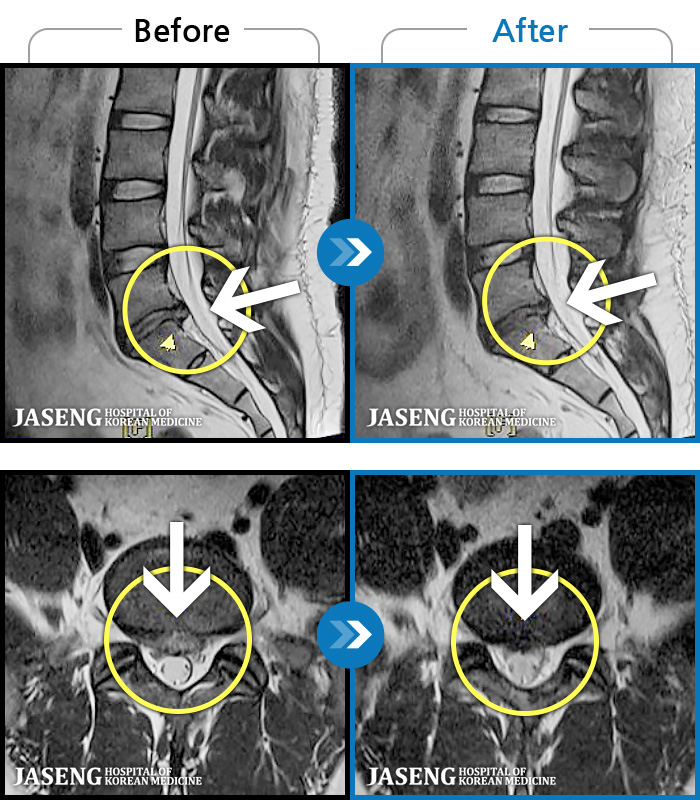

MRI ġ

1,245 MRI ũ ʸ Ȯϼ.